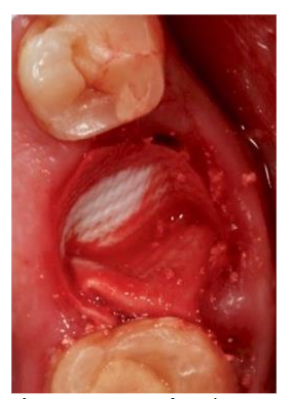

Described here is one case our of 20, wherein a healthy male patient without any medical condition, reported at the dental office with fractured lower mandibular first molar (#36). A treatment plan of socket preservation and implant placement was given to him to which he readily agreed. Minimally invasive tooth extraction was done under local anesthesia and care was taken not to damage either of the bony walls.

After extraction, the socket was not compressed so that the width of the ridge is maintained. Maxresorb bone graft (Botiss, Germany) was placed in the socket.

A single layer of collagen membrane, Ossix plus membrane (Dentsply Sirona, Germany) was placed on the bone graft and 3-0 silk sutures were placed in a manner to hold the tissue and membrane in place however no attempt was made to approximate the open ends of soft tissue. It should also be noted that in such cases achieving primary closure is not possible unless the mucoperiosteum flap is not mobilized.